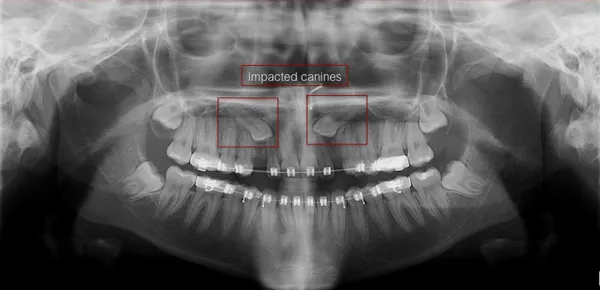

An impacted tooth essentially means that it is blocked, stuck, or unable to fully erupt and function properly. The upper canine teeth are the second most common teeth after third molars (wisdom teeth) to become impacted. Impacted canines require surgical treatment (exposure) to enable them to erupt.

Recognition of impacted eyeteeth at an early age is essential. Thorough examination of the teeth accompanied by panoramic x-rays and/or individual x-rays is important. Once the cause of the impaction is determined, the available treatment options can be established.

Impacted eyeteeth can be located on the palatal side (roof of the mouth) of the dental arch, above the roots of the adjacent teeth, or out to the facial side of the dental arch.